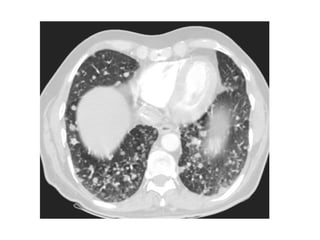

a) Usual Interstitial Pneumonia (UIP) : Honeycombing

-Also known as Idiopathic pulmonary fibrosis (IPF)

-Apicobasal gradient is even better seen on high-resolution

CT images

-Together with subpleural reticular opacities and

macrocystic honeycombing combined with traction

bronchiectasis, the apicobasal gradient represents a trio

of signs that is highly suggestive of UIP

-Therefore, UIP should be considered in patients who

present with low lung volumes, subpleural reticular

opacities, macrocystic honeycombing, and traction

bronchiectasis, the extent of which increases from the

apex to the bases of the lungs

Distribution of UIP, the distribution is subpleural with an apicobasal

gradient (red area in a), CT shows honeycombing (green areas

in c), reticular opacities (blue areas in c), traction bronchiectasis

(red area in c), and focal ground-glass opacity (gray area in c)

Honey combing

-Defined by the presence of small cystic spaces

with irregularly thickened walls composed of

fibrous tissue

-Honeycomb cysts often predominate in the

peripheral and subpleural lung regions

regardless of their cause

-Subpleural honeycomb cysts typically occur in

several contiguous layers, this finding can allow

honeycombing to be distinguished from

paraseptal emphysema in which subpleural

cysts usually occur in a single layer

Honeycombing & traction bronchiectasis in UIP

Honeycombing comprises reticular densities caused by the thick walls of the cysts.

Whenever you see a chest film with long standing reticulation with a lower lobe and

peripheral preference

A, Unenhanced axial high-resolution CT through left mid (A) and lower (B) lung

show peripheral honeycombing, which is greatest in lower lobe,

accompanied by traction bronchiectasis and scattered peripheral reticular

opacities. Honeycombing is most prominent feature in this patient, typical for

idiopathic pulmonary fibrosis